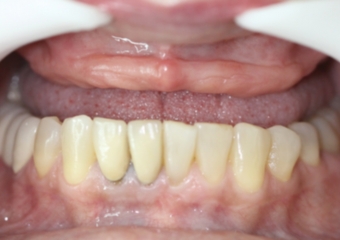

Prótese Provisória

Sorriso Final com a prótese provisória